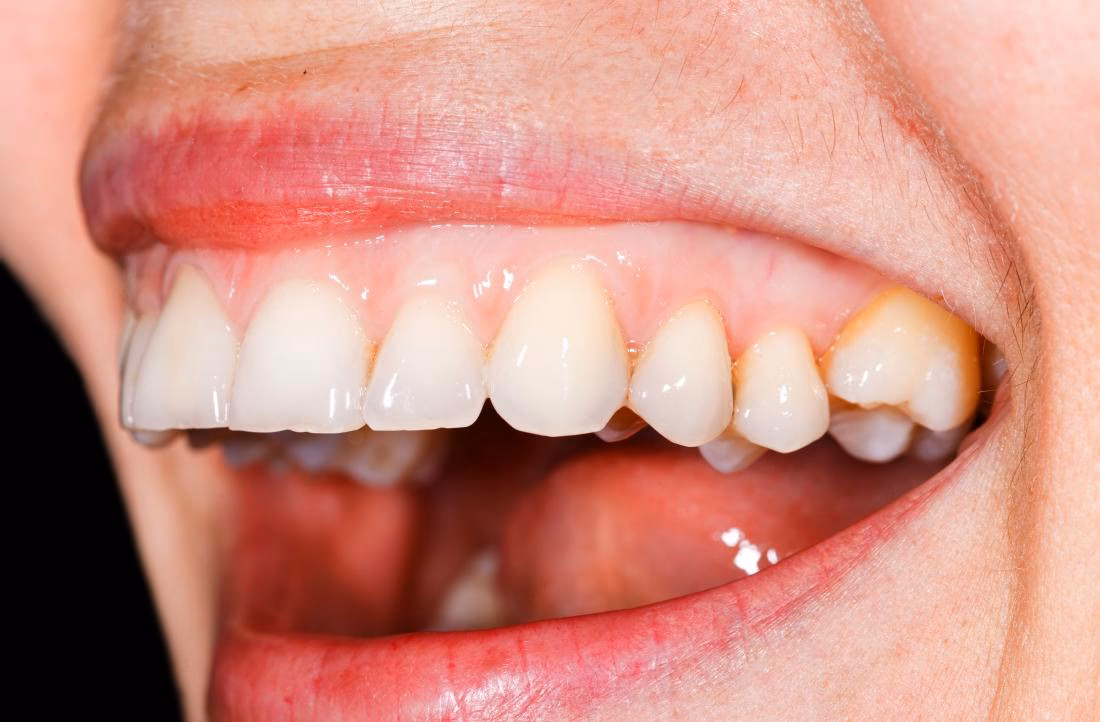

Hvorfor Bliver Tandkødet Blegt ved Anæmi?

Den sunde, lyserøde farve, vi normalt forbinder med tandkød, skyldes det rige netværk af små blodkar (kapillærer), der ligger lige under den tynde overflade af slimhinden. Blodets røde farve, som kommer fra de iltede røde blodlegemer, skinner igennem og giver tandkødet sin karakteristiske farve. Når en person lider af anæmi, er der færre røde blodlegemer i cirkulation. Dette betyder, at blodet bogstaveligt talt er mindre rødt. Som et resultat bliver den rige farve i tandkødet mindre intens, hvilket får det til at se blegt, falmet eller hvidligt ud. Dette fænomen kaldes undertiden "anæmi-tandkød" og er et klassisk klinisk tegn. Palenessen er ikke kun begrænset til tandkødet; den kan også ses på tungen og på indersiden af kinderne og læberne. Derfor er blegt tandkød et vigtigt advarselstegn, som bør føre til en samtale med en læge.